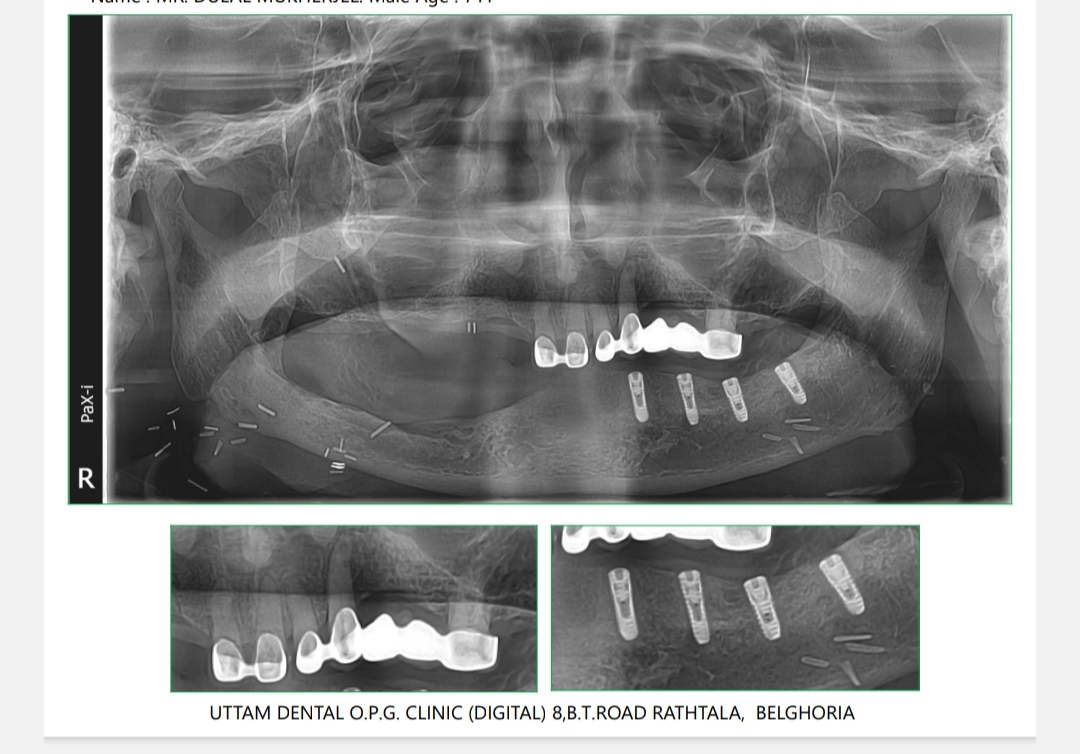

Dental Implants

Dental implants are long-term investment in oral health. Unlike other tooth replacement options, such as dentures or bridges, dental implants can last a lifetime with proper care and maintenance. They do not require any special cleaning or adhesives, and they do not put strain on adjacent teeth like bridges can.